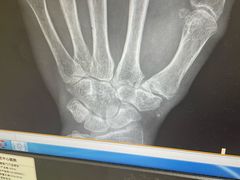

• -上海市普陀区中心医院

路人飞 | 24-09-10

报错